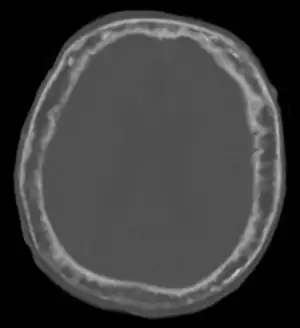

| "مقطعنگاری رایانهای جمجمه بیمار ۹۲ ساله نشان دهنده افزایش ضخامت دیواره جمجمه در مراحل پیشرفته بیماری پاژه." | |